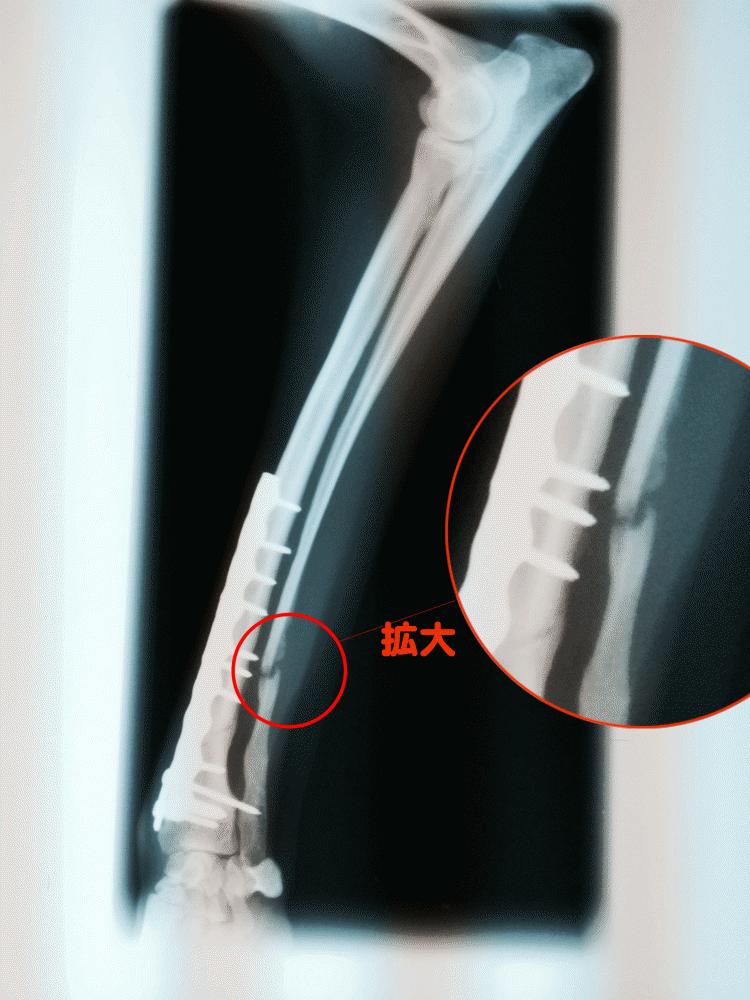

「イタグレ骨折」気候の変化と共にこの記事へのアクセスが増えています!!!!!現在、過去3年間のアクセスデータを集計、分析しています。何か傾向が見つかればブログに書きます。今の時点で感じている事は、寒い季節は筋肉が減ります、暖かくなったらといって急な運動は筋肉が減った愛犬には過酷な過酷な状況になります。これからもっともっと気候はよくなるので先ずはゆっくりじっくり散歩から始めましょう。ちなみに我が家のBuono!は寒い時期は30分から1時間のんびり歩いてから芝で遊んでいます。近所に芝はいっぱいありますが、4月に入ってからまだ芝では遊ばせていません、それよりもじっくりほぼ毎日60分ぐらい歩いています。骨折は痛みと共に脳の記憶にも残ります。悲しい記憶です。